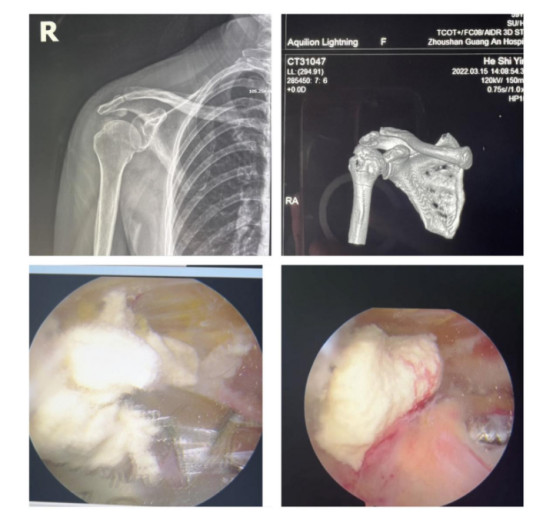

賀大媽慕名來廣安醫(yī)院找羅軍主任就診,面對羅醫(yī)生,賀大媽哭訴:“羅醫(yī)生,我真想剁下自己的這只胳膊。”羅軍主任根據(jù)患者的癥狀拍片,診斷為岡上肌鈣化性肌腱炎,隨后,羅醫(yī)生為李大媽進(jìn)行了肩關(guān)節(jié)鏡微創(chuàng)手術(shù),竟從她的右肩“擠”出“牙膏”。

鈣化性肌腱炎是一種自限性疾病,就是疾病發(fā)生發(fā)展到一定程度后,經(jīng)長期機體調(diào)節(jié)能夠控制病情發(fā)展并逐漸恢復(fù)痊愈。它分為四個階段:鈣化前期、鈣化形成期、鈣化吸收期、鈣化后期,往往在“鈣鹽斑塊”吸收時,疼痛最劇烈,賀大媽就正處于“吸收期”。

是不是只要病人撐得住,讓鈣鹽吸收就沒事了?羅軍主任表示,經(jīng)保守治療無法緩解或病程長的患者,應(yīng)盡早采取手術(shù)治療。而且,部分患者鈣鹽無法完全吸收,拖下去只會使病情惡化,造成肩膀肩袖肌腱的損傷。

羅軍主任表示,很多人會把肩痛都?xì)w因于肩周炎,這是一個很大的誤區(qū)。其實,肩痛人群中只有15%左右是肩周炎,大部分肩膀疼痛由于肩袖損傷、肩峰撞擊征、鈣化性肌腱炎。而大多數(shù)人也因此認(rèn)為忍一忍就會自愈,常常延誤治療,關(guān)節(jié)鏡微創(chuàng)治療鈣化性肌腱炎,可以快速緩解疼痛,同時可以修復(fù)肩袖損傷,清理肩膀骨刺。